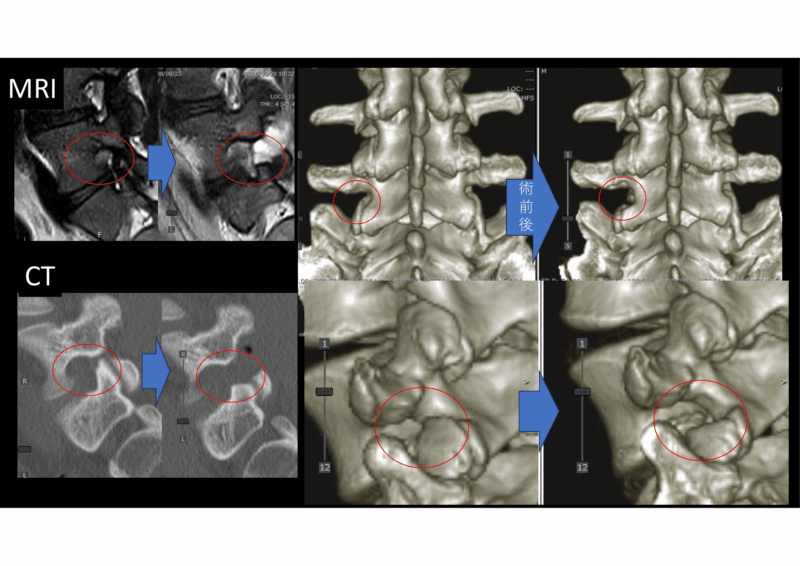

そして術前後の画像です。後方からしっかり除圧して、神経根尾側のヘルニアもしっかりとる、というコンセプト。これなら神経を痛めません。